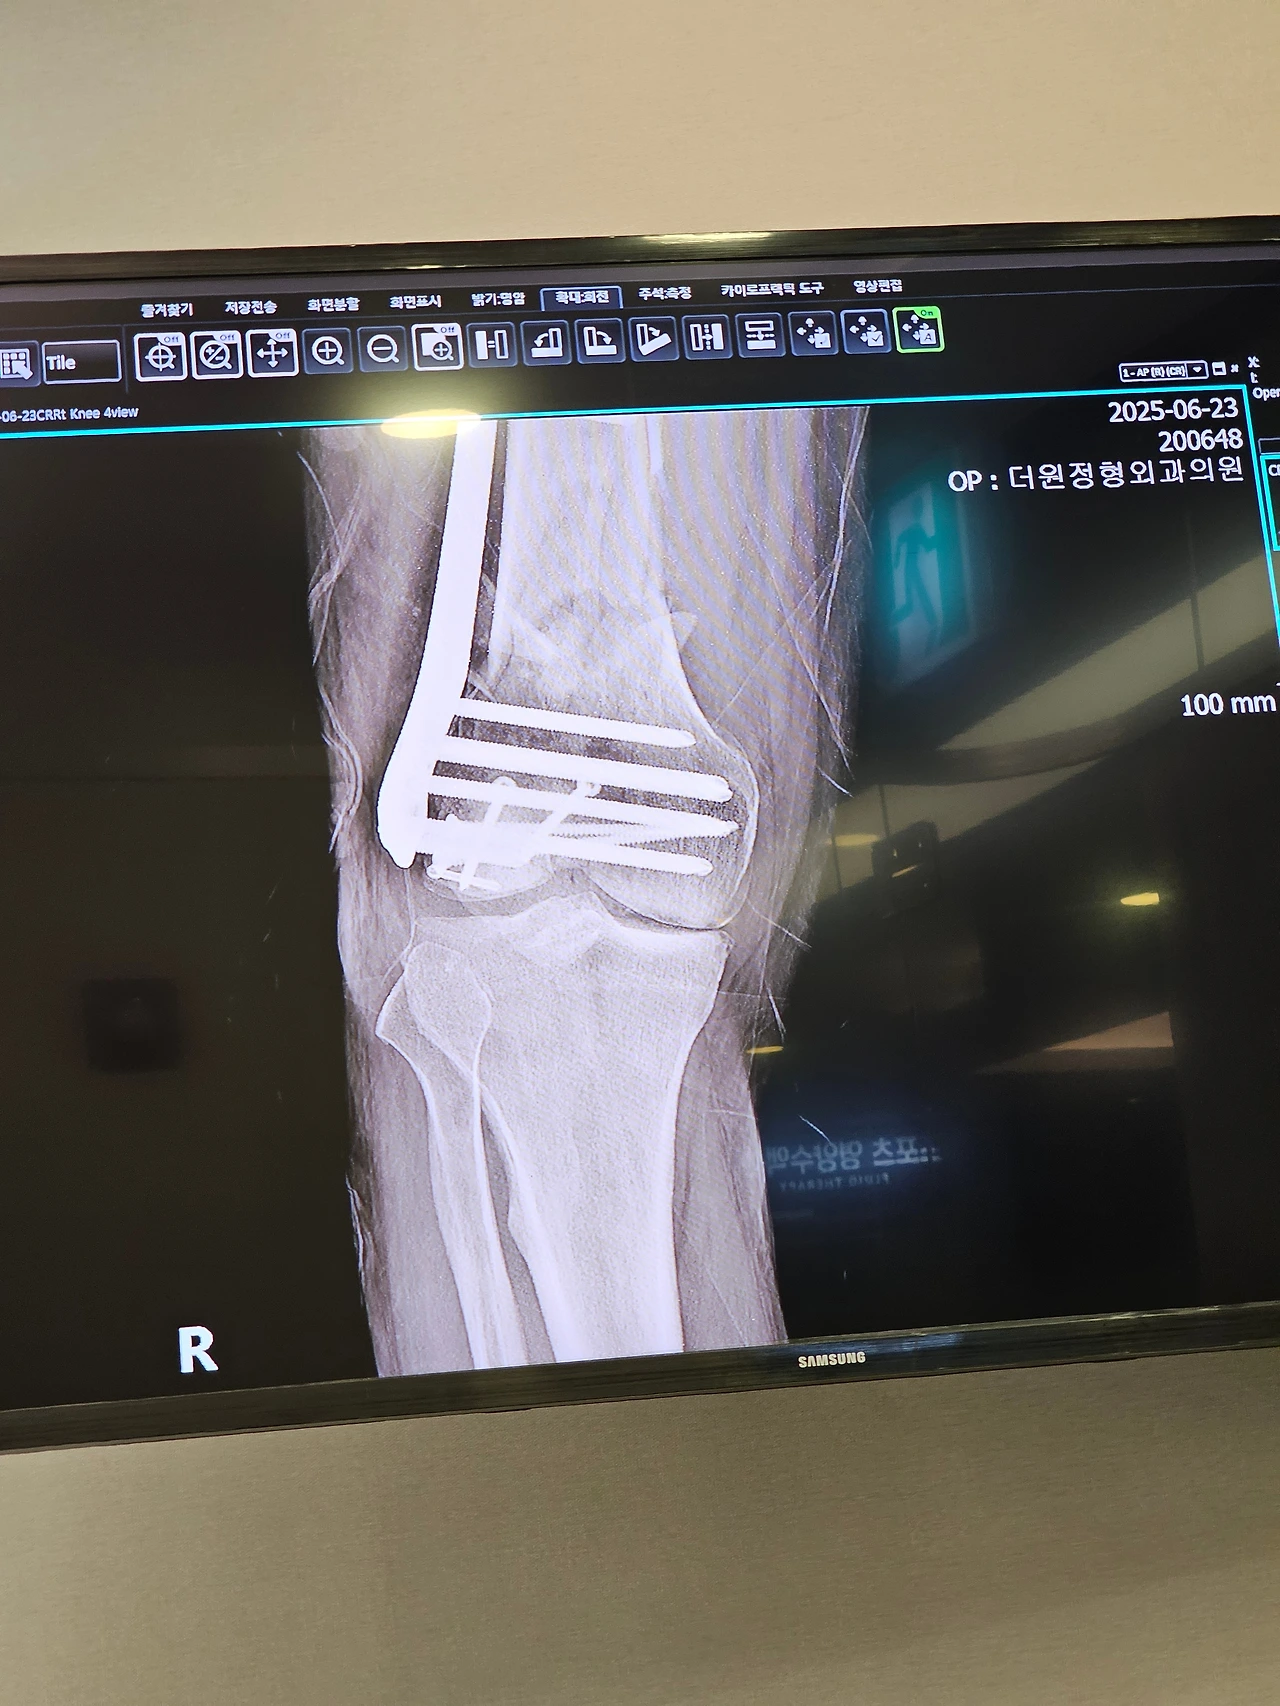

갑작스럽게 교통사고가 났어요. 살면서 처음 겪어보는 큰 사고였고 하필 크게 다쳤네요. 오른쪽 대퇴골 원위부 골절이라고 무릎 바로 위쪽이 복합골절 즉 분쇄 골절 되었고 턱관절은 5 부위로 쪼겨져서 얼굴이 말이 아닙니다.

수술부위는 세 군데, 허벅지 대퇴골 수술, 오른쪽 눈 밑 안와골절 수술, 턱 골절 수술. 날짜를 나눠서 진행하지 않고 다행히도 마취 한 번에 수술을 받았습니다.

덕분에 수술시간이 많이 길어진 것으로 알고 있고요. 총 10시간이 지났다고 하더군요. 대퇴골 수술은 생각보다 금방 끝난 것 같은데 턱 수술이 오래 걸린 듯합니다. 그 작은 부위에 나사를 12개를 박았거든요.